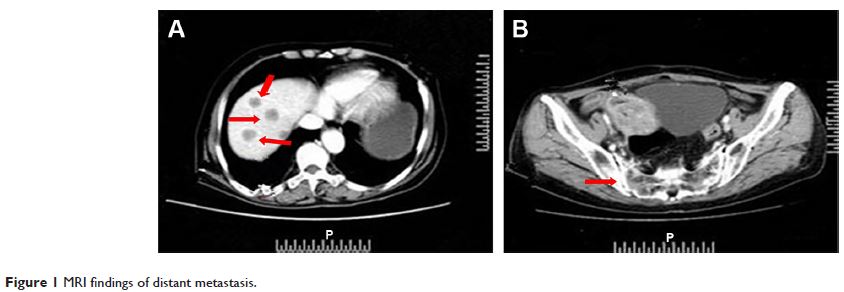

Case Report

- 作者:Yong Zhang, Yalong Qi, Axiang Wang, Baozhen Ma, Xiaomin Fu, Lingdi Zhao, Quanli Gao

- 期刊:OncoTargets and Therapy